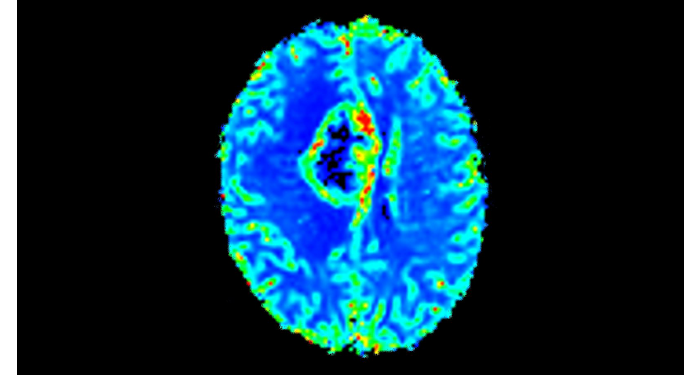

70% of radiologists consider neuro indications to be challenging, mostly due to a lack of appropriate imaging and visualization techniques¹. Philips aims to provide the best possible diagnostic clarity and treatment guidance for all patients with neurological disorders. By leveraging our dStream digital platform, this year, we are introducing, a set of novel imaging and visualization strategies. These may empower you to resolve complex neuro questions with more certainty, as well as unlock new neuro territories in advanced Neurofunctional applications. This is a key step towards elevating neuro diagnostics and ultimately touching more lives with MR imaging. ¹ TMTG Market Survey 2016

New neuro applications